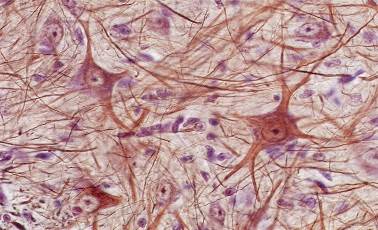

Мир нейроцитов: исследование нервных клеток